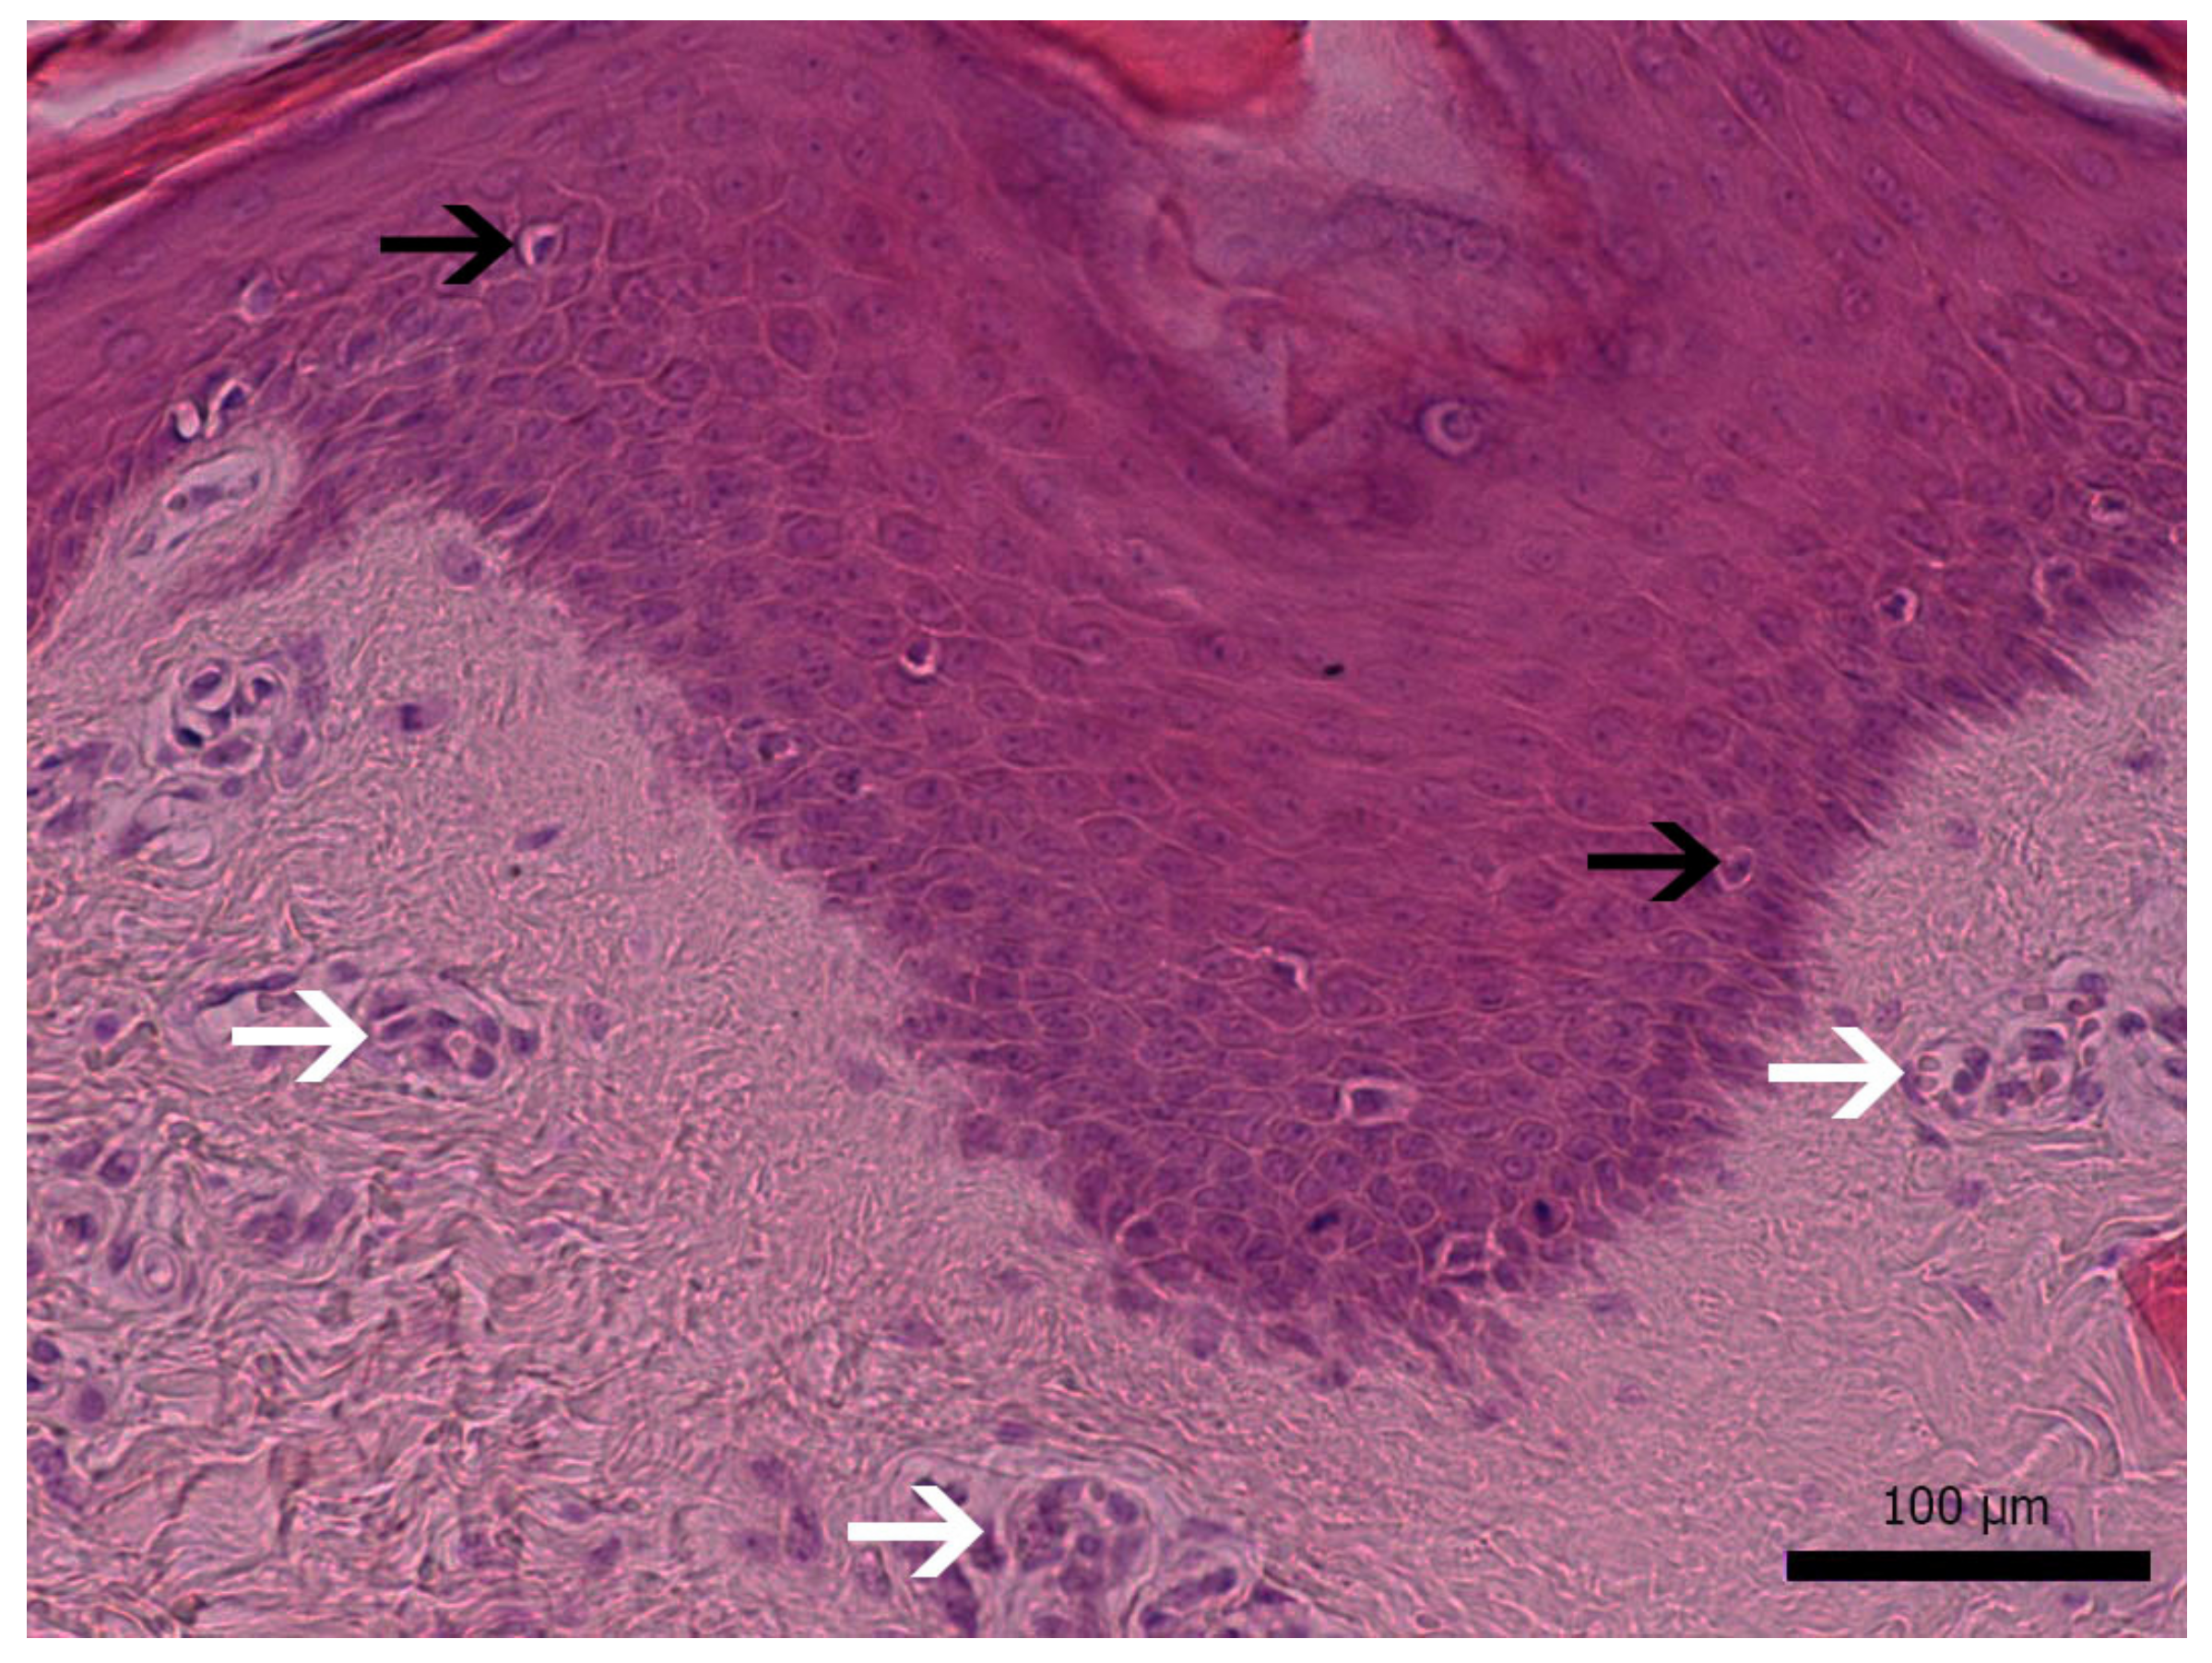

3.1. Diseased Animals and Histology of the Affected Skin